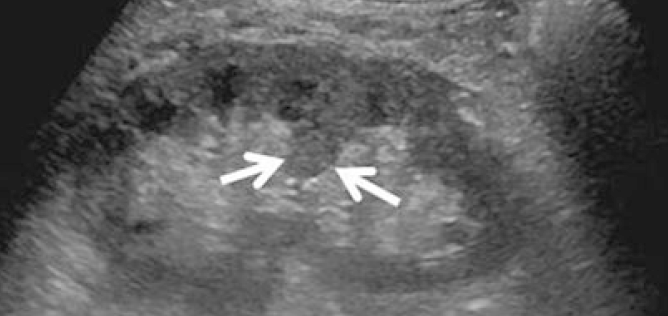

5-Fetal lobulations

في مرحلة تطور الجنين تتكون الكلية عن طريق تلاحم عدة فصوص lobes. وهذه الفصوص قد تستمر إلى مابعد مرحلة البلوغ. تظهر بشكل تموجات في القشرة الخارجية للكلية. من المهم أن لا نخطئ في تشخصيها كندبة scar أو ورم في الكلية.